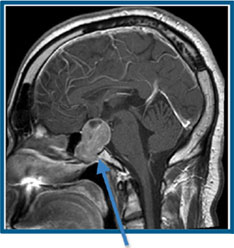

| Pituitary tumor |

Acoustic neuroma is a rare, non-malignant tumor that develops on the main nerve leading from the inner ear to the brain. The pituitary gland is an organ that produces hormones which regulate important functions of the body and is located in the middle of the base of the brain.

The risk of cancer of the pituitary gland more was more than twice as high among women who used a cell phone for less than five years as compared to never users. Although the risk was elevated for women who used a cell phone for ten or more years (about 60% greater than never users), this effect was not significant. Since this may be the first study to find an association between cell phone use and pituitary cancer, further research on this cancer is necessary.